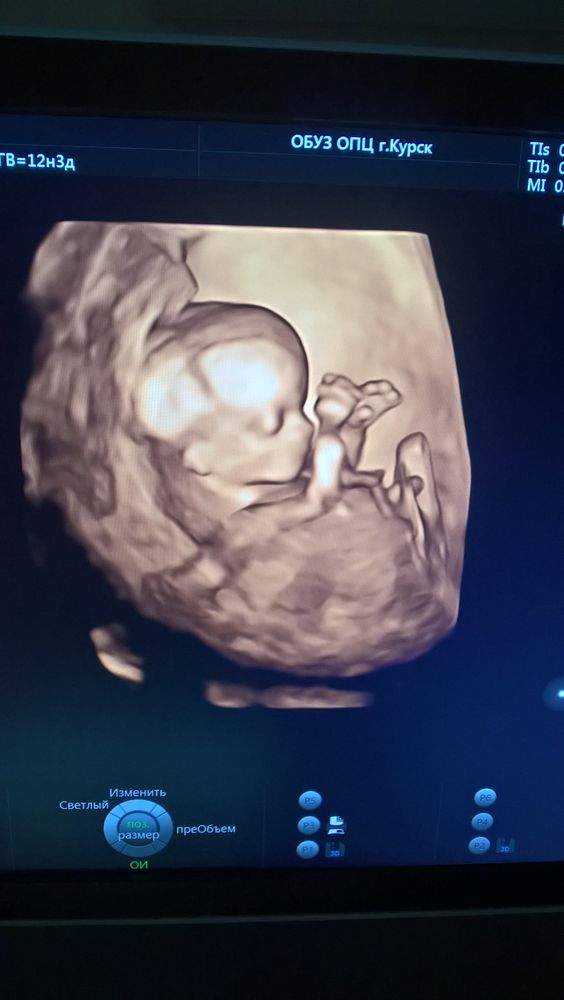

Мария

Я два раза пыталась сделать 3д узи , все время отворачивается ) Но один раз пришла , узист сказал съесть что-нибудь сладкое и походить минут 20, пришла , он повернулся) на фото как будто улыбается 😀